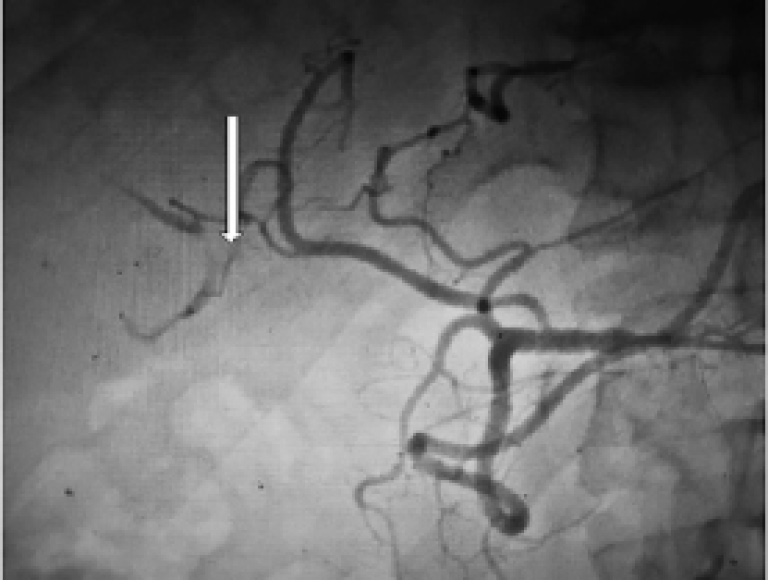

Результаты и их обсуждение. Для проведения клеточной терапии госпитализирован пациент А. 56 лет с диагностированным циррозом печени алиментарной этиологии класса А по Чайлд-Пью, осложнённым портальной гипертензией с варикозным расширением вен пищевода 1-й ст, гиперспленизмом и спленомегалией. Была применена клеточная терапия в виде введения в артериальное русло печени аутологичных мезенхимальных стволовых клеток в количестве 25 ×106 (рис. 1).

Рис. 1. Целиография пациента А. Стрелкой обозначена правая печеночная артерия, в которую вводились аутологичные МСК